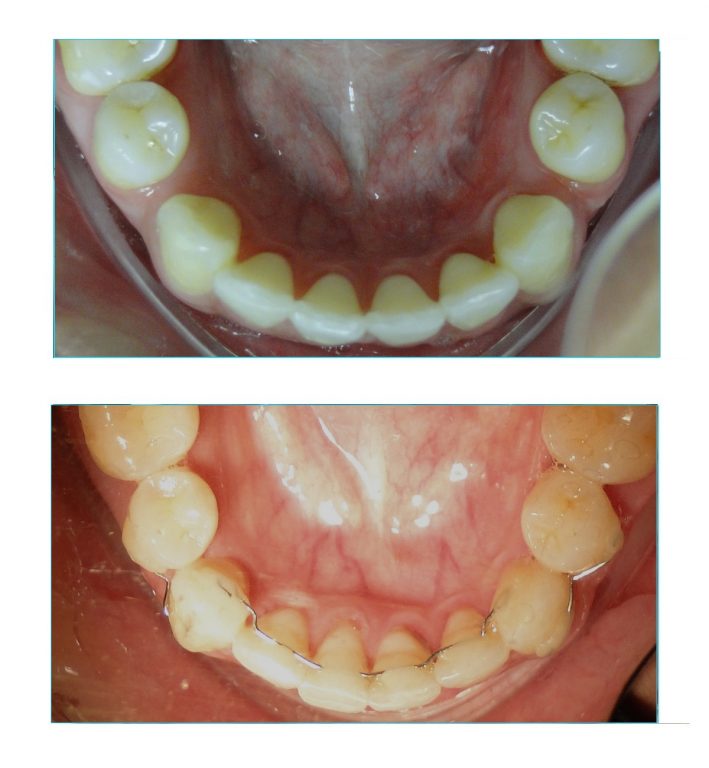

O caso mostrado aqui foi iniciado por outro profissional que indicou as extrações.

Porém, em certo ponto do tratamento, os espaços pararam de fechar. Por mais que se aumentasse a força aplicada, os dentes já não respondiam com movimentação.

Esse efeito é muito comum, principalmente em casos com quatro extrações de pré-molares em que não havia muita falta de espaço nas arcadas.

Ou seja, os tratamentos de biprotursão, são os que apresentam maior risco de fechamento incompleto dos espaços.

A paciente chegou com essas separações e foi muito difícil conseguir o fechar completamente os espaços.

Esse caso foi muito difícil, pois foi iniciado de forma errada por outro profissional, que no meio do tratamento já não conseguia mais fechar o espaço. Tive que desfazer tudo e levei quase dois anos para fechar completamente os espaços.

Ainda assim, mantenho essa paciente (e todos os outros também) monitorando anualmente a estabilidade do caso.